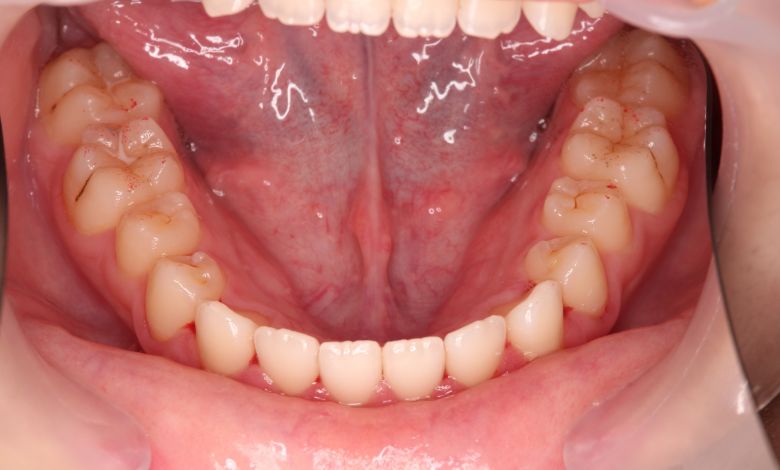

下の前歯が3本、強く重なり合って生えており、歯並びの乱れが目立つ

下顎の歯列では、前歯部に強い重なりが見られ、中切歯および側切歯がねじれたり前後にずれて生えているのが確認できる

精密検査の結果、抜歯を行わずに歯列弓を拡大する治療方針を選択。歯が正しい位置に並ぶスペースを

確保したことで、歯列は自然なU字型に整い、叢生が解消されました。見た目の改善だけでなく、

咀嚼機能の向上や清掃性の改善といった機能面での効果も期待できます。